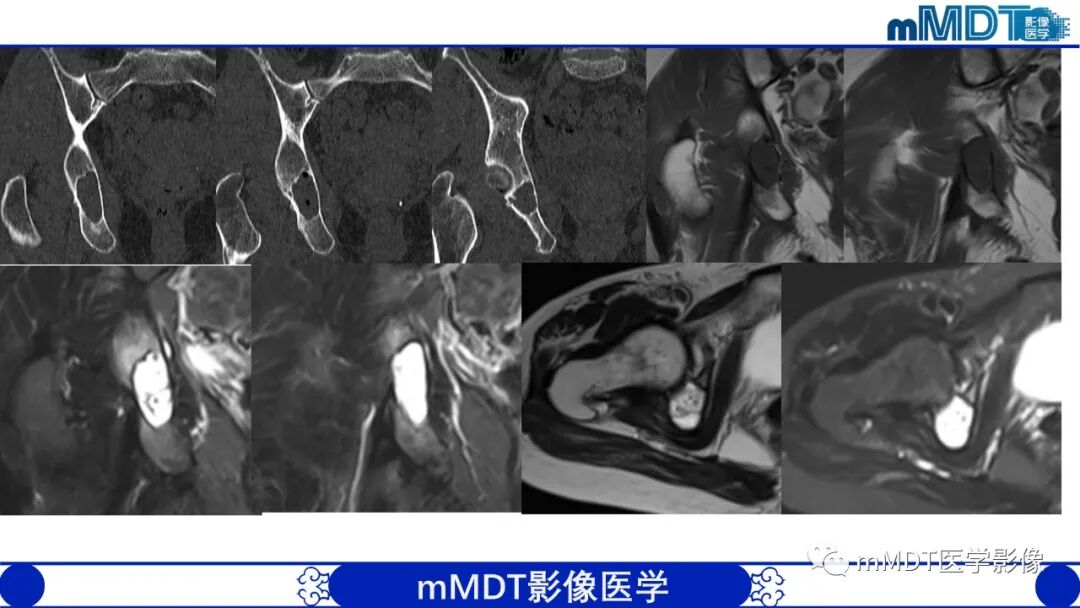

1.坐骨股骨间隙(ischiofemoralspace,IFS)变窄,坐骨股骨间隙是坐骨结节外侧骨皮质到股骨小转子内侧骨皮质的最窄距离,正常坐骨股骨间隙正常人群组为23±8mm,若间隙﹤12mm可视为狭窄。

2.股方肌间隙(quadratus femorisspace,QFS)变窄,股方肌间隙是股方肌通过的最窄间隙,其后内侧边界是腘绳肌肌腱止点的外上表面,前外侧边界是髂腰肌肌腱或股骨小转子的后内侧表面,测量这两个边界之间的最短距离。正常股方肌间隙人群组为12±4mm,若间隙﹤7mm可视为狭窄。

3.股方肌以位于坐骨股骨间隙最狭窄处的肌腹为中心出现水肿信号挤压变形。长期病变患者可出现股方肌脂肪浸润或肌萎缩。